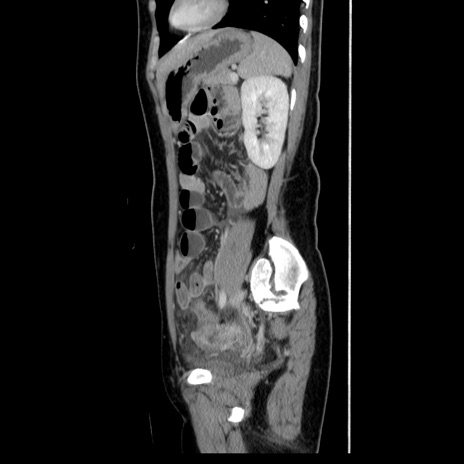

症例39(矢状断像)

【症例】40歳代女性

【主訴】上下腹部痛

【現病歴】2日目から下腹部痛あり。夜間は痛みで眠れなかった。昨日より上腹部痛と下痢が出現。臥位で痛みは軽快したため、休んでいた。本日になって臥位でも立位でも痛みが強くなってきたため救急要請。

【既往歴】子宮内膜症

【身体所見】部:平坦・軟、左上下腹部に圧痛あり、反跳痛あり。

【データ】WBC 21800、CRP 26.78

CT